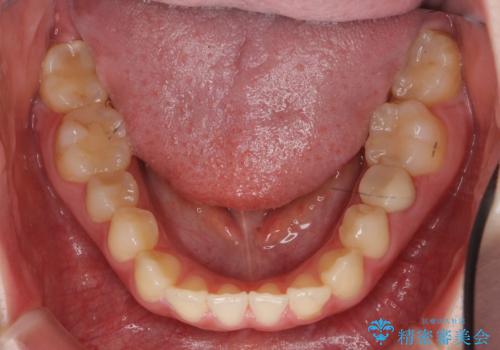

犬歯のねじれ 上の歯が引っ込んでいる

- 前歯の並びを気にして来院。

インビザラインで、上の前歯をやすり掛けして並べました。